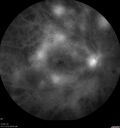

Pan Retinal Laser from original DRS study in the 1970s - 50 years later281 views67 year old female with diabetes since age 8. She had heavy PRP laser to both eyes in the 1970s by Lloyd M. Aiello, M.D, the father of PRP laser. Her vision is poor now, 1/200 OD and 20/200 OS.Oct 13, 2021

Pan Retinal Laser from original DRS study in the 1970s - 50 years later294 views67 year old female with diabetes since age 8. She had heavy PRP laser to both eyes in the 1970s by Lloyd M. Aiello, M.D, the father of PRP laser. Her vision is poor now, 1/200 OD and 20/200 OS.Oct 13, 2021

Pan Retinal Laser from original DRS study in the 1970s - 50 years later296 views67 year old female with diabetes since age 8. She had heavy PRP laser to both eyes in the 1970s by Lloyd M. Aiello, M.D, the father of PRP laser. Her vision is poor now, 1/200 OD and 20/200 OS.Oct 13, 2021